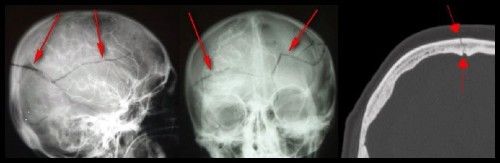

Nous trouvons quatre différents types de fractures crâniennes :

Fracture linéaire

C’est la plus fréquente. Elle se situe, la plupart du temps, sur les côtés du crâne. Une distance entre les os plus ou moins marquée peut être aussi notée.